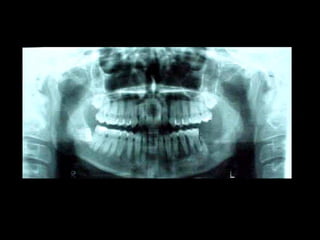

Queratoquiste odontogénico

Otro caso